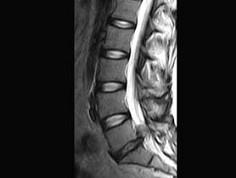

问题 男,50岁,有腰腿疼痛2个月,疼痛可向左下肢放射,请结合所提供图像,选出最佳选项 ( )

选项 A、L/S椎间盘膨出 B、L/L椎间盘膨出 C、L/L椎间盘突出 D、椎间盘变性 E、L/S椎间盘突出

答案 E